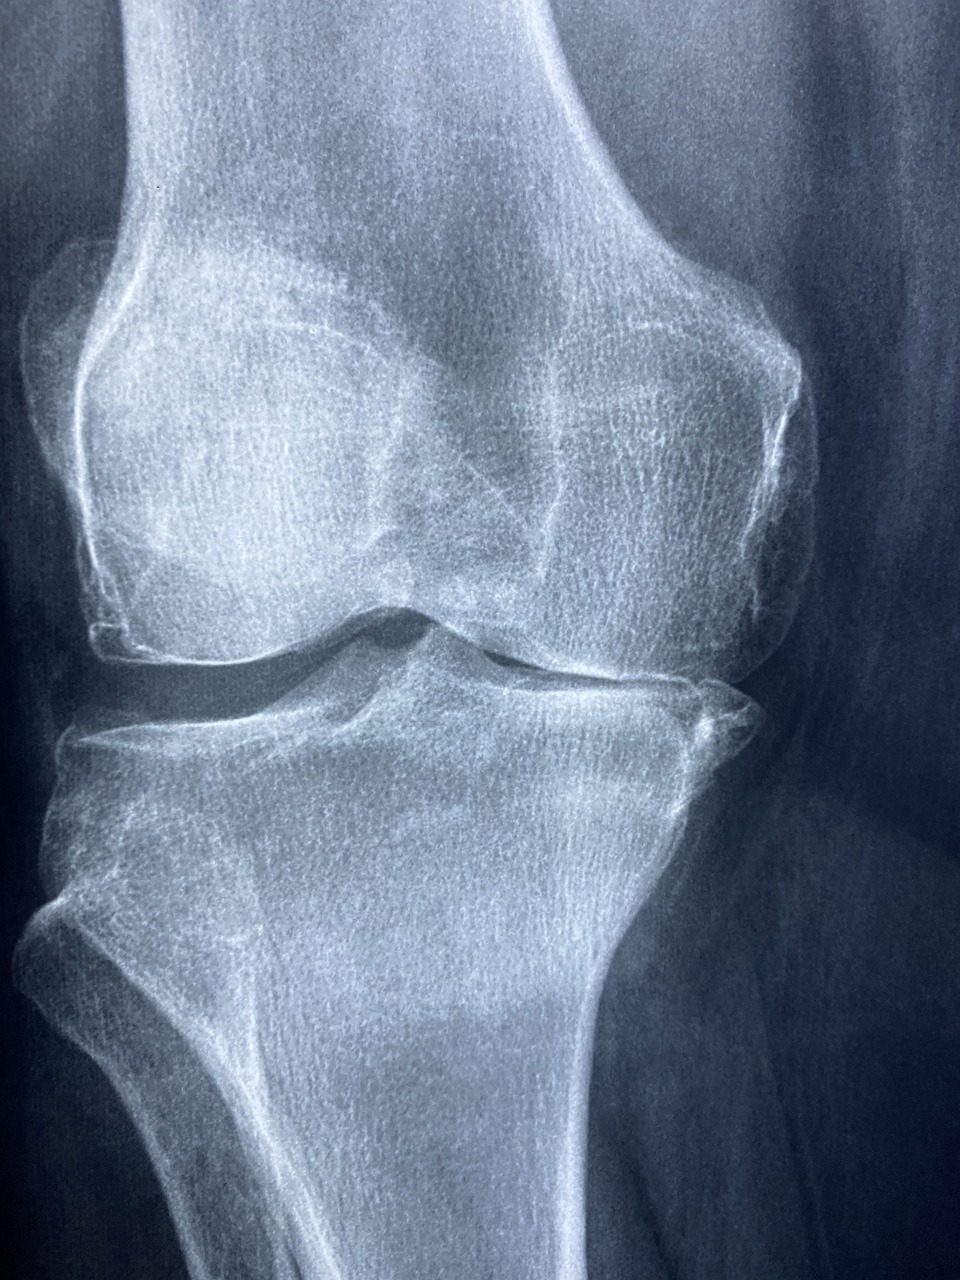

퇴행성 관절염은 65세 이상 노인의 약 70~80%가 겪는 흔한 질병입니다. 특히 무릎은 체중 부하가 심한 부위이기 때문에 관절이 닳고, 물렁뼈가 손상되면서 통증과 부종이 생깁니다. 이럴 때 근본적인 해결책은 바로 무릎 인공관절 수술입니다. 인공 관절을 삽입해 통증을 줄이고 기능을 되살리는 방식입니다.